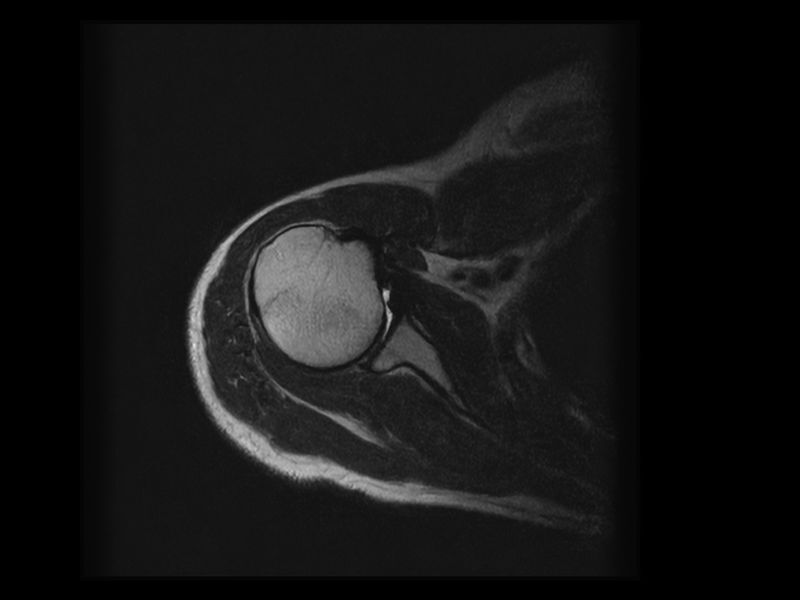

Esaote introduces Artificial Intelligence into its MRI systems as a fully integrated and customized solution. The new technological platform, e‑SPADES, consisting of advanced HW and sophisticated SW algorithms such as HyperClarity delivers unparalleled image quality.

HyperClarity

Step into a new era for Esaote systems with HyperClarity, powered by SwiftMR™, a trademark of AIRS Medical Inc. This advanced integrated feature significantly enhances image quality by improving resolution, reducing noise, and providing physicians with a powerful tool for more consistent clinical outcomes.

Clinical Images